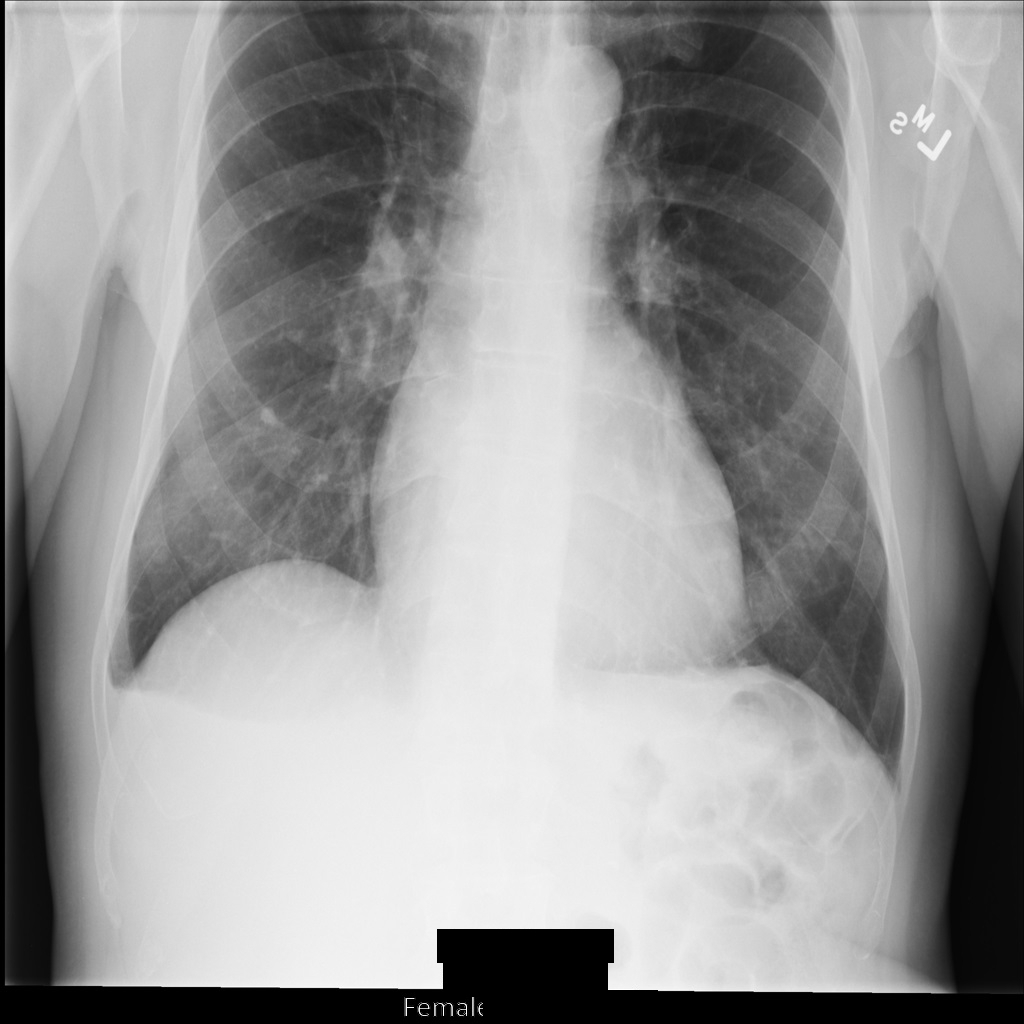

After de-identifying the image using REDACT_SENSITIVE_TEXT_CLEAN_DESCRIPTORS, the image

looks like this. Notice that not all the burned-in text at the bottom of the

image has been redacted. The text Female is still shown, because

PatientSex (0010,0040) isn't one of the default DICOM infoTypes.